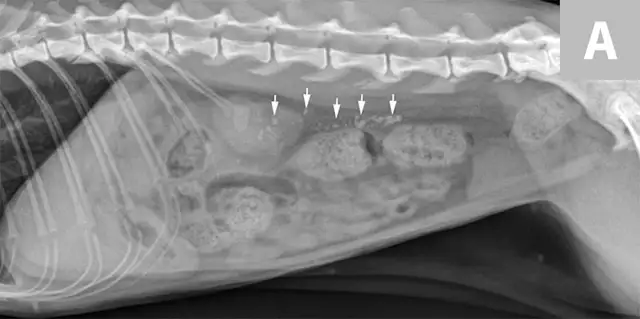

FIGURE 7A

Lateral abdominal radiograph of a cat with multiple, small, oval mineral opacities superimposed over the ventral aspect of the retroperitoneal space (arrows). These mineral opacities are arranged linearly extending from the caudal aspect of the kidneys to the level of the urinary bladder.